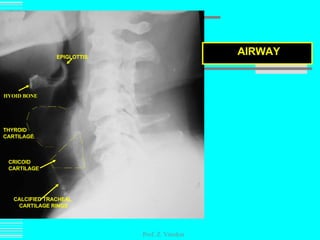

Prof. Z. Vinokur AIRWAY EPIGLOTTIS HYOID BONE CALCIFIED TRACHEAL CARTILAGE RINGS THYROID  CARTILAGE CRICOID  CARTILAGE

Prof. Z. VinokurAIRWAY EPIGLOTTIS HYOID BONE CALCIFIED TRACHEAL CARTILAGE RINGS THYROID CARTILAGE CRICOID CARTILAGE